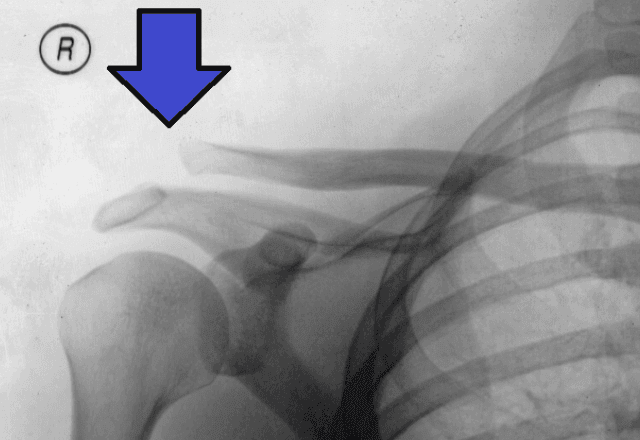

O tratamento com ondas de choque ganha espaço e respaldo científico para a recuperação de lesões musculoesqueléticas. O tratamento utiliza ondas acústicas de choque para estimular a reabilitação de danos em músculos, ossos, ligamentos, tendões, cartilagens e nervos – contusões normalmente ligadas à prática esportiva, acelerando o retorno do paciente às atividades físicas.